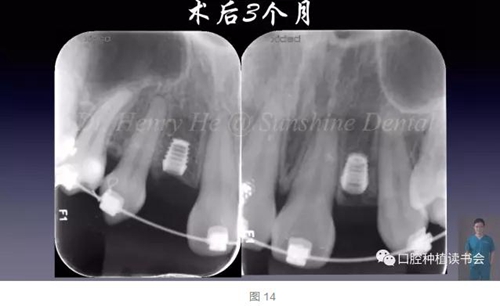

3個(gè)月后進(jìn)行了微創(chuàng)的二期手術(shù)(圖14),暴露植體,上愈合帽(圖15)